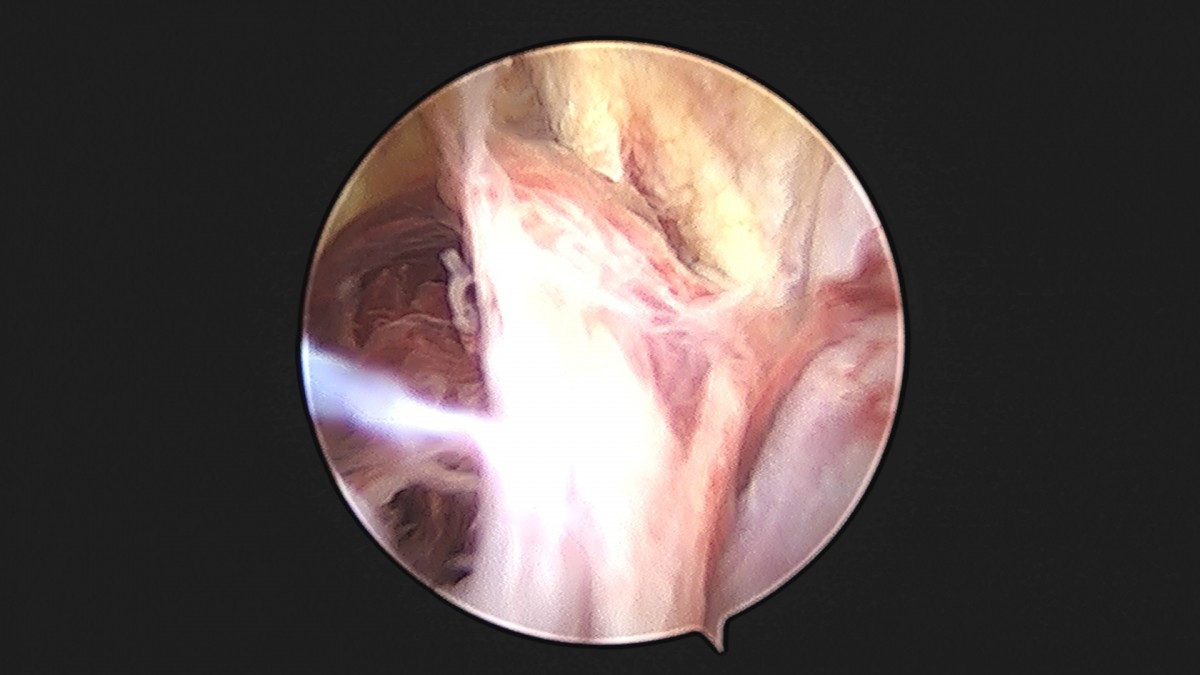

이재상원장님 발목 인대 봉합술 박찬O 환자

dae765e4d9ac96aee867c9d6292d8784_1758007285_6203.jpg